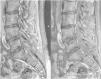

Over the years, at different times, he was treated with codeine, tramadol, methadone and oxycodone, but the analgesic outcome was insufficient. Magnetic resonance imaging of the lumbar spine showed signs of multisegmental bone infarction (Figure 2). At 29 years old, after 10 years of conservative treatment with severe pain measured by the Visual Analogue Scale (VAS) of 8/10, an intrathecal test with morphine (200mcg) was performed. The test was satisfactory, which motivated the implantation of an intrathecal infusion pump. The patient has been using the device for approximately nine years. It was replaced two years ago, due to an ulceration that appeared in the topography of the implant. Currently, he uses an electronic device with a capacity of 40 ml of medication - in this case, morphine 10 mg / ml, in a daily dose of 4705 mcg. He works as a physiotherapist and he does not need to go to the emergency department for analgesia anymore. He also does not demand analgesics orally and has mild pain (average daily VAS of 2/10).